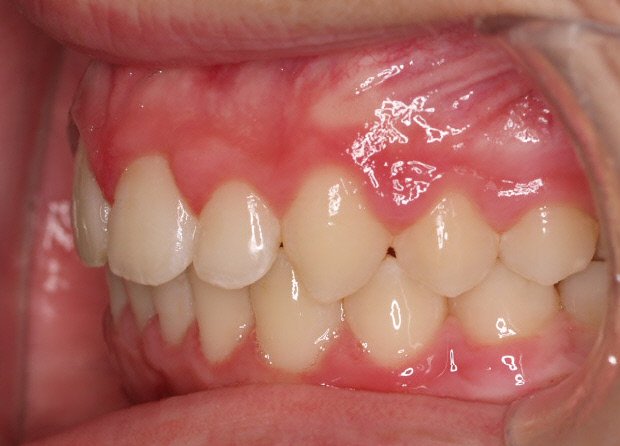

Paciente de 13 años que presenta sonrisa disarmónica.

- Clase I esquelética

- Clase I molar

- DDM +++ anterior

- Sobremordida

Decidimos extraer los 4 primeros premolares.

A los dos años quitamos aparatología fija y la paciente entra en fase de contención encantada con su nueva sonrisa.

Lleva férulas ESSIX a la noche más una contención fija inferior de canino a canino.